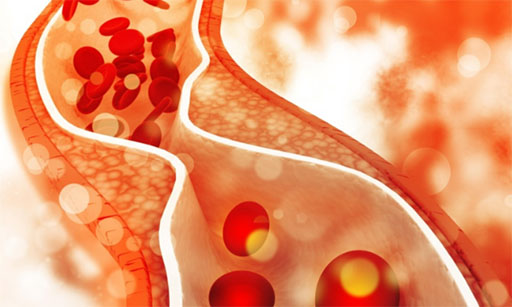

De hecho, eligió trazar un panorama sobre las últimas investigaciones en materia de tratamiento de cardiopatías. Explicó el desarrollo de modelos de las mecánicas de los vasos, el flujo sanguíneo y las válvulas cardíacas, a fin de utilizarlos para la optimización del diseño de dispositivos implantados, como las válvulas cardíacas artificiales y los stents para las arterias coronarias. También se refirió al desarrollo de herramientas que les permitan a los médicos tomar decisiones basándose en un análisis detallado de las características de cada paciente, como guía para el tratamiento de enfermedades cardiovasculares.

“Una arteria se puede modelizar al igual que una tubería por la que corre un líquido, sólo que deformable. Incluso a pesar de que las propiedades de la pared arterial son especiales, las ecuaciones son las mismas. Con ese propósito, por ejemplo, se hacen ensayos numéricos sobre la arteria carótida, para conocer sus propiedades mecánicas, que se visualizan en una curva de tensión/deformación, de la misma manera que se hace con una tubería de hormigón en ingeniería civil”, detalló.

En los ejemplos que exhibió en la conferencia, por caso, mostró animaciones con remolinos de partículas de sangre producidos en la circulación por las arterias. “Mediante este tipo de modelizaciones, se puede predecir una acumulación de colesterol en una arteria y si va a ser necesario un stent”, aseguró, con el fin de abrir en el futuro esa arteria, una vez obstruida. “La simulación también permite predecir la rotura de una pared arterial debida al depósito de placas”, sostuvo.